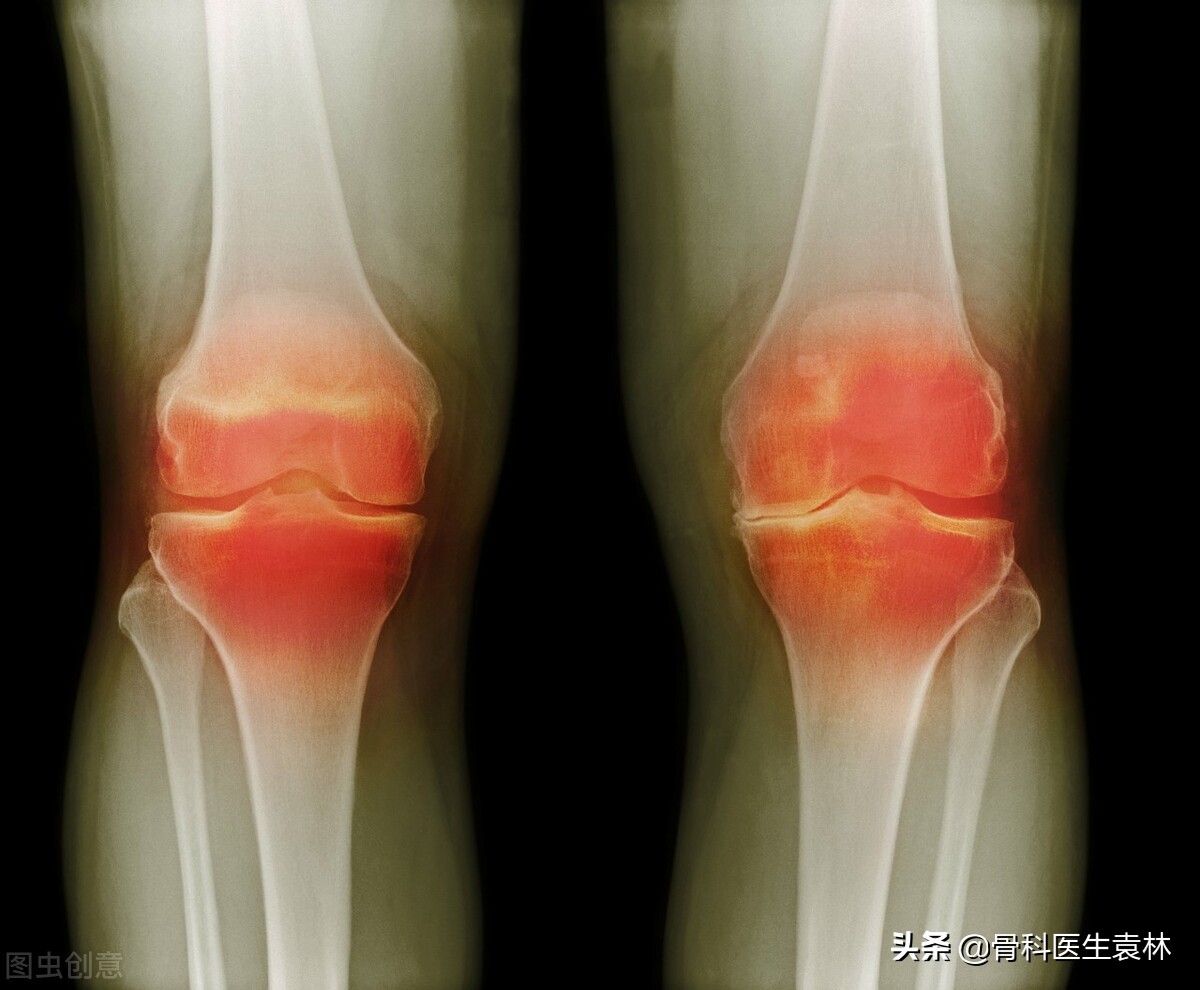

骨关节炎是骨科中非常常见的一种疾病,在生活中有很多人已经出现骨关节炎的早期的症状表现,有的患者的症状不是很严重,从而导致忽略了骨关节炎的严重性,可能大家在生活中经常的听说骨关节炎,但是有的人对骨关节炎的了解并不全面,今天我就给大家说一下,关节出现这5种情况,千万不要忽视了。

关节出现这5种情况,千万别当回事!当心是骨关节炎